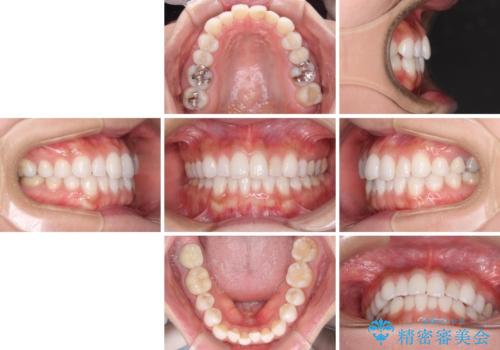

- 前歯が気になるとのことで来院された患者様です。

歯列不正は軽微であったため、インビザライン・ライトにより、費用を抑えて矯正治療を行うこととしました。

短期間で気になる前歯の歯列を改善することができました。